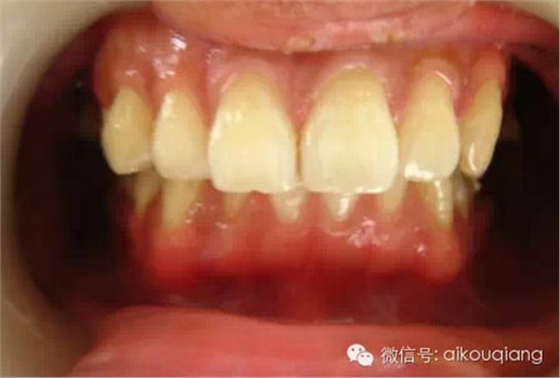

定期洗牙是目前最有效的治療牙周疾病的方式。下面是洗牙前后的對(duì)比圖:

洗牙(潔治)后,潔白如一